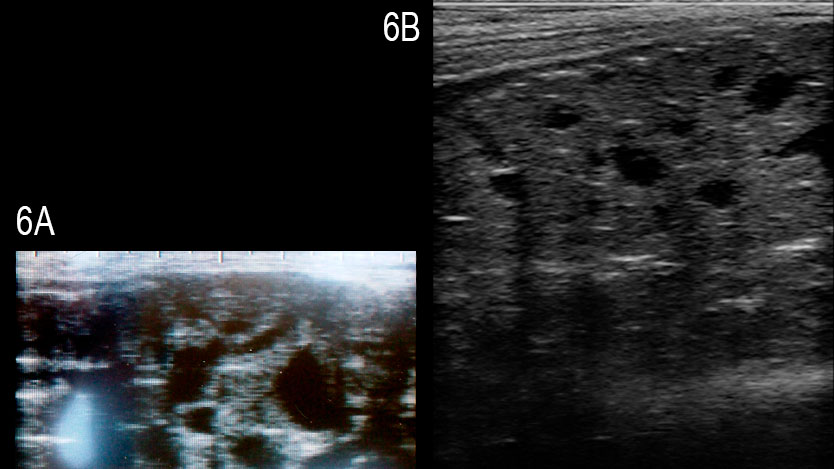

Les études sur l'utilisation pratique de l'échographie dans la reproduction des verrats sont rares. Le diamètre des testicules a été déterminé afin de le relier avec le nombre total de spermatozoïdes produits dans un éjaculat moyen (Clark et al., 2003) ou pour évaluer le développement pubertaire (Ford et Wise, 2010). La corrélation du diamètre des deux testicules et du nombre total de spermatozoïdes a été mauvaise, au moins chez les verrats de plus de 8 mois; la détermination de la taille testiculaire des plus jeunes verrats, d'environ 4 mois, a semblé utile pour la prédiction du volume des testicules et de la production de sperme lorsque le verrat avait atteint la maturité. Il y a un rapport récent sur un verrat Large White infertile avec une dégénérescence multikystique de la glande bulbo-utétrale; dans la glande affectée on visualise des kystes anéchogéniques solides et bien définis de différentes tailles (Figure 6, Grahofer et al., 2016)

En résumé, l'échographie de l'appareil génital du verrat est une modalité de diagnostic viable qui peut fournir des informations précieuses sur la fonction et la santé du tissu. Même si l'utilisation pratique est actuellement limitée, l'auteur est fermement convaincu que l'utilisation de cette méthode (et d'autres comme le Doppler couleur [Figure 7A et B]) obtiendra une plus grande utilisation chez les vétérinaires porcins comme un outil pour prédire le rendement potentiel des éjaculats et pour diagnostiquer avec précision les problèmes de subfertilité et d'infertilité associée à des tissus malades.